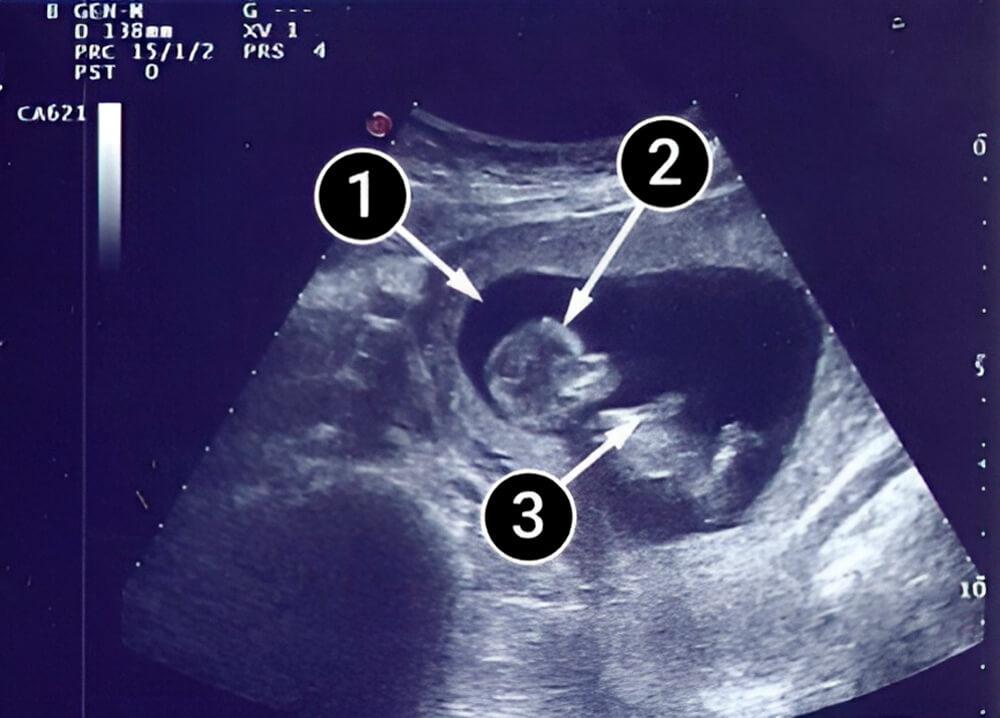

¿Qué se puede ver en la ecografía/ultrasonido?

El bebé se acuesta boca arriba, con la cabeza y las nalgas contra la pared uterina. Se deberían ver con claridad el contorno de la cabeza con frente, nariz, párpados y labios. La cabeza parece algo grande, pero pronto se volverá más proporcional al resto del cuerpo. Los músculos de la boca ya están funcionando, por lo que se puede ver al bebé abrir, cerrar y apretar los labios. El bebé también puede levantar y bajar los párpados.

Los brazos del bebé deben estar visibles; y una de sus posiciones favoritas en el útero, es cruzar los brazos sobre el pecho. Las piernas dobladas son visibles. El área oscura y nebulosa representa el líquido amniótico, que está fluyendo de manera constante.